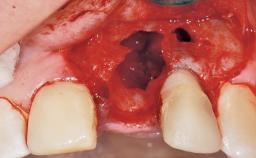

Immediate Flapless Placement of an Implant in a Maxillary Left Central Incisor Site

Placement Protocol Immediate implant placement

Socket Integrity Damage to one or more bone walls

Bone Volume Damage to one or more socket walls